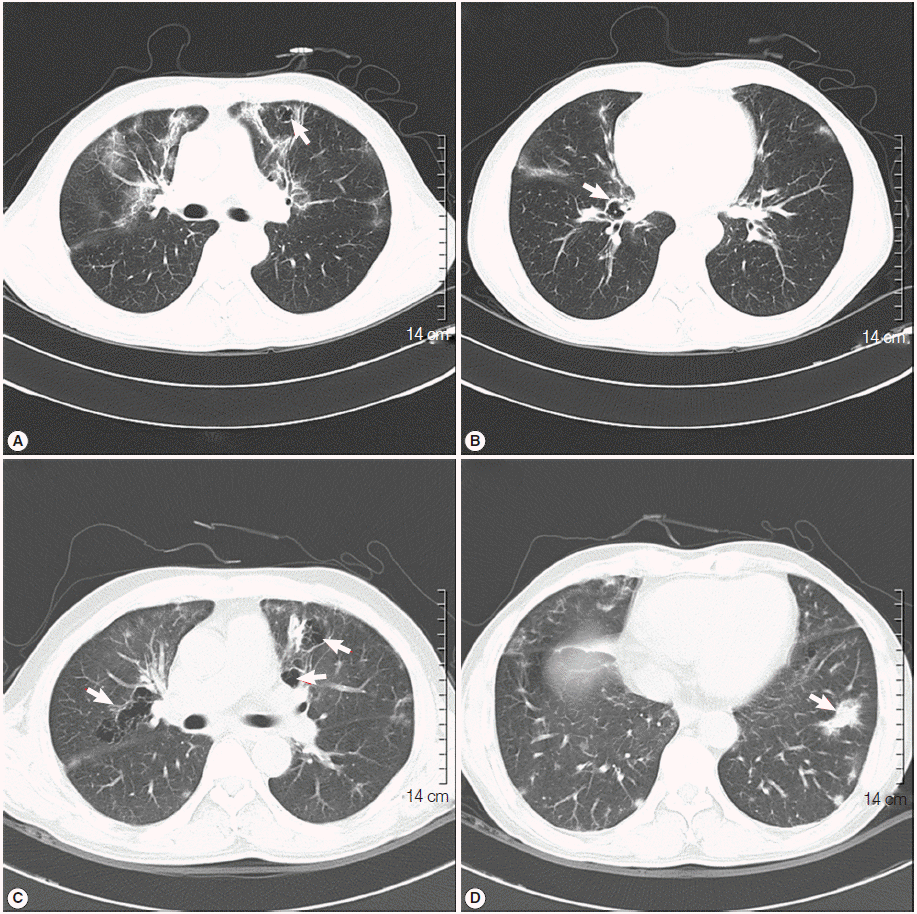

A 50-year-old male visited the outpatient clinic and complained of fever, poor oral intake, and weight loss (6 kg loss in 2 months). Routine laboratory tests and a chest X-ray were performed. Complete blood counts revealed mild leucopenia (WBC 3,720/μl), mild anemia (Hb 11.2 g/dl), and mild eosinophilia (830/μl), however, a normal platelet level (246,000/μ) was observed. Liver function tests showed elevated liver enzymes (AST 61 IU/L, ALT 74 IU/L, and GGT 215 IU/L), and serologic studies for hepatitis B virus, hepatitis C virus, human immunodeficiency virus (HIV), and syphilis were negative. A routine chest X-ray yielded streaky and fibrotic lesions in both lungs (Fig. 1A), which led to further evaluation using contrast chest computed tomography (CT). The chest CT revealed multifocal peribronchial patchy ground-glass opacities in both lungs with septated cystic lesions in the left upper lobe, and the right lower lobe (Fig. 2A, B).

Bronchoscopy was performed, but no endobronchial lesions were observed. Bronchoalveolar lavage (BAL) was performed in the right middle lobe. Cell counts in BAL revealed a lymphocyte-dominant leukocytosis (white cells 342/μl, neutrophils 9%, lymphocytes 37%, eosinophils 5%, and macrophages 49%). Further analysis of lymphocyte subsets showed a predominance of cytotoxic T cells (cytotoxic T cells 98.3%, T helper cells 1.7%, natural killer cells 3%, and B cells 0.1%). Cytologic studies, acid-fast bacillus stain, and PCR for tuberculosis and non-tuberculotic mycobacteria in the BAL fluid exhibited negative results. A tuberculin skin test and interferon-γ release assay (Quantiferon®; Carnegie, Victoria, Australia) were also negative. A video-assisted wedge resection of the left upper lobe was performed. Upon histological examination, hematoxylin and eosin (H&E) staining revealed eosinophilic frothy exudates in alveolar spaces accompanied by mild interstitial inflammation, and Grocott-Gomori’s methenamine silver (GMS) stains, performed during the histological examination, revealed many cystic- and trophic-form organisms (arrows) in the alveolar exudate, consistent with P. jirovecii infection (Fig. 3). Trimethoprim-sulfamethoxazole (TMP-SMX) was administered orally (2 double strength TMP-SMX tablets every 8 hr) [11]. The patient’s fever subsided within 3 days (from 38.5˚C to 37.0˚C), and the streaky and fibrotic lesions observed in both lungs on the chest X-ray were also markedly improved (Fig. 1B) after 12 days of TMP-SMX administration, which enabled the patient to be discharged.

TMP-SMX treatment continued to be administrated for additional 17 days following the patient’s discharge from the hospital. However, the patient complained of cough again, and a follow-up chest X-ray showed aggravation of the streaky and fibrotic lesions in both lungs (Fig. 1C). The patient was readmitted to the hospital, and chest CT was rechecked. A follow-up chest CT revealed an aggravation of multifocal peribronchial ground-glass opacity and septated cystic lesions in both upper lungs, and a newly appeared consolidation in the left lower lobe (Fig. 2C, D). P. jirovecii was clinically suspected to be resistant to TMP-SMX, and molecular studies carried out using PCR with primers Dp15 (5´-TCTGAATTTTATAAAGCGCCTACAC-3´) and Dp800 (5´-ATTTCATAAACATCATGAACCCG-3´) demonstrated mutations at codons 55 and 57 of the dihydropteroate synthase (DHPS) gene as a previous report [12].

Primaquine (4 mg/kg/day intravenous once daily) and clindamycin (600 mg intravenous every 8 hr) were administrated for 3 weeks in place of the TMP-SMX. Consequently, the cough was resolved, and a follow-up chest X-ray showed improvement of the streaky and fibrotic lesions in both lungs (Fig. 1D). We strongly suspected that HIV infection was an underlying condition, and rechecked the HIV immunoassay, which was determined to be positive. Further evaluation of HIV infection was performed; the titer of HCV RNA was determined to be 110,000 copies/ml, and the number of T helper cells in the peripheral blood was only 3/μl. Antiviral treatment regimen targeting the HIV was initiated, including lopinavir (800 mg/day), ritonavir (200 mg/day), lamivudine (300 mg/day), and zidovudine (600 mg/day), and the patient was discharged.